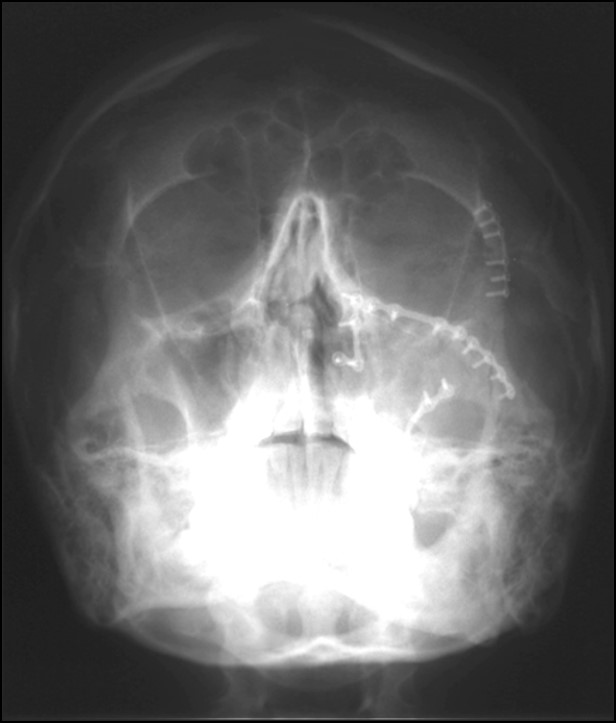

Στοματικό & Γναθοπροσωπικό Τραύμα